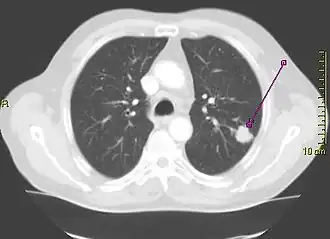

Computed tomography of the chest

A "lung window" CT scan showing a lung cancer in the left lung

Computed tomography of the chest or chest CT is a group of computed tomography scan protocols used in medical imaging to evaluate the lungs and search for lung disorders.